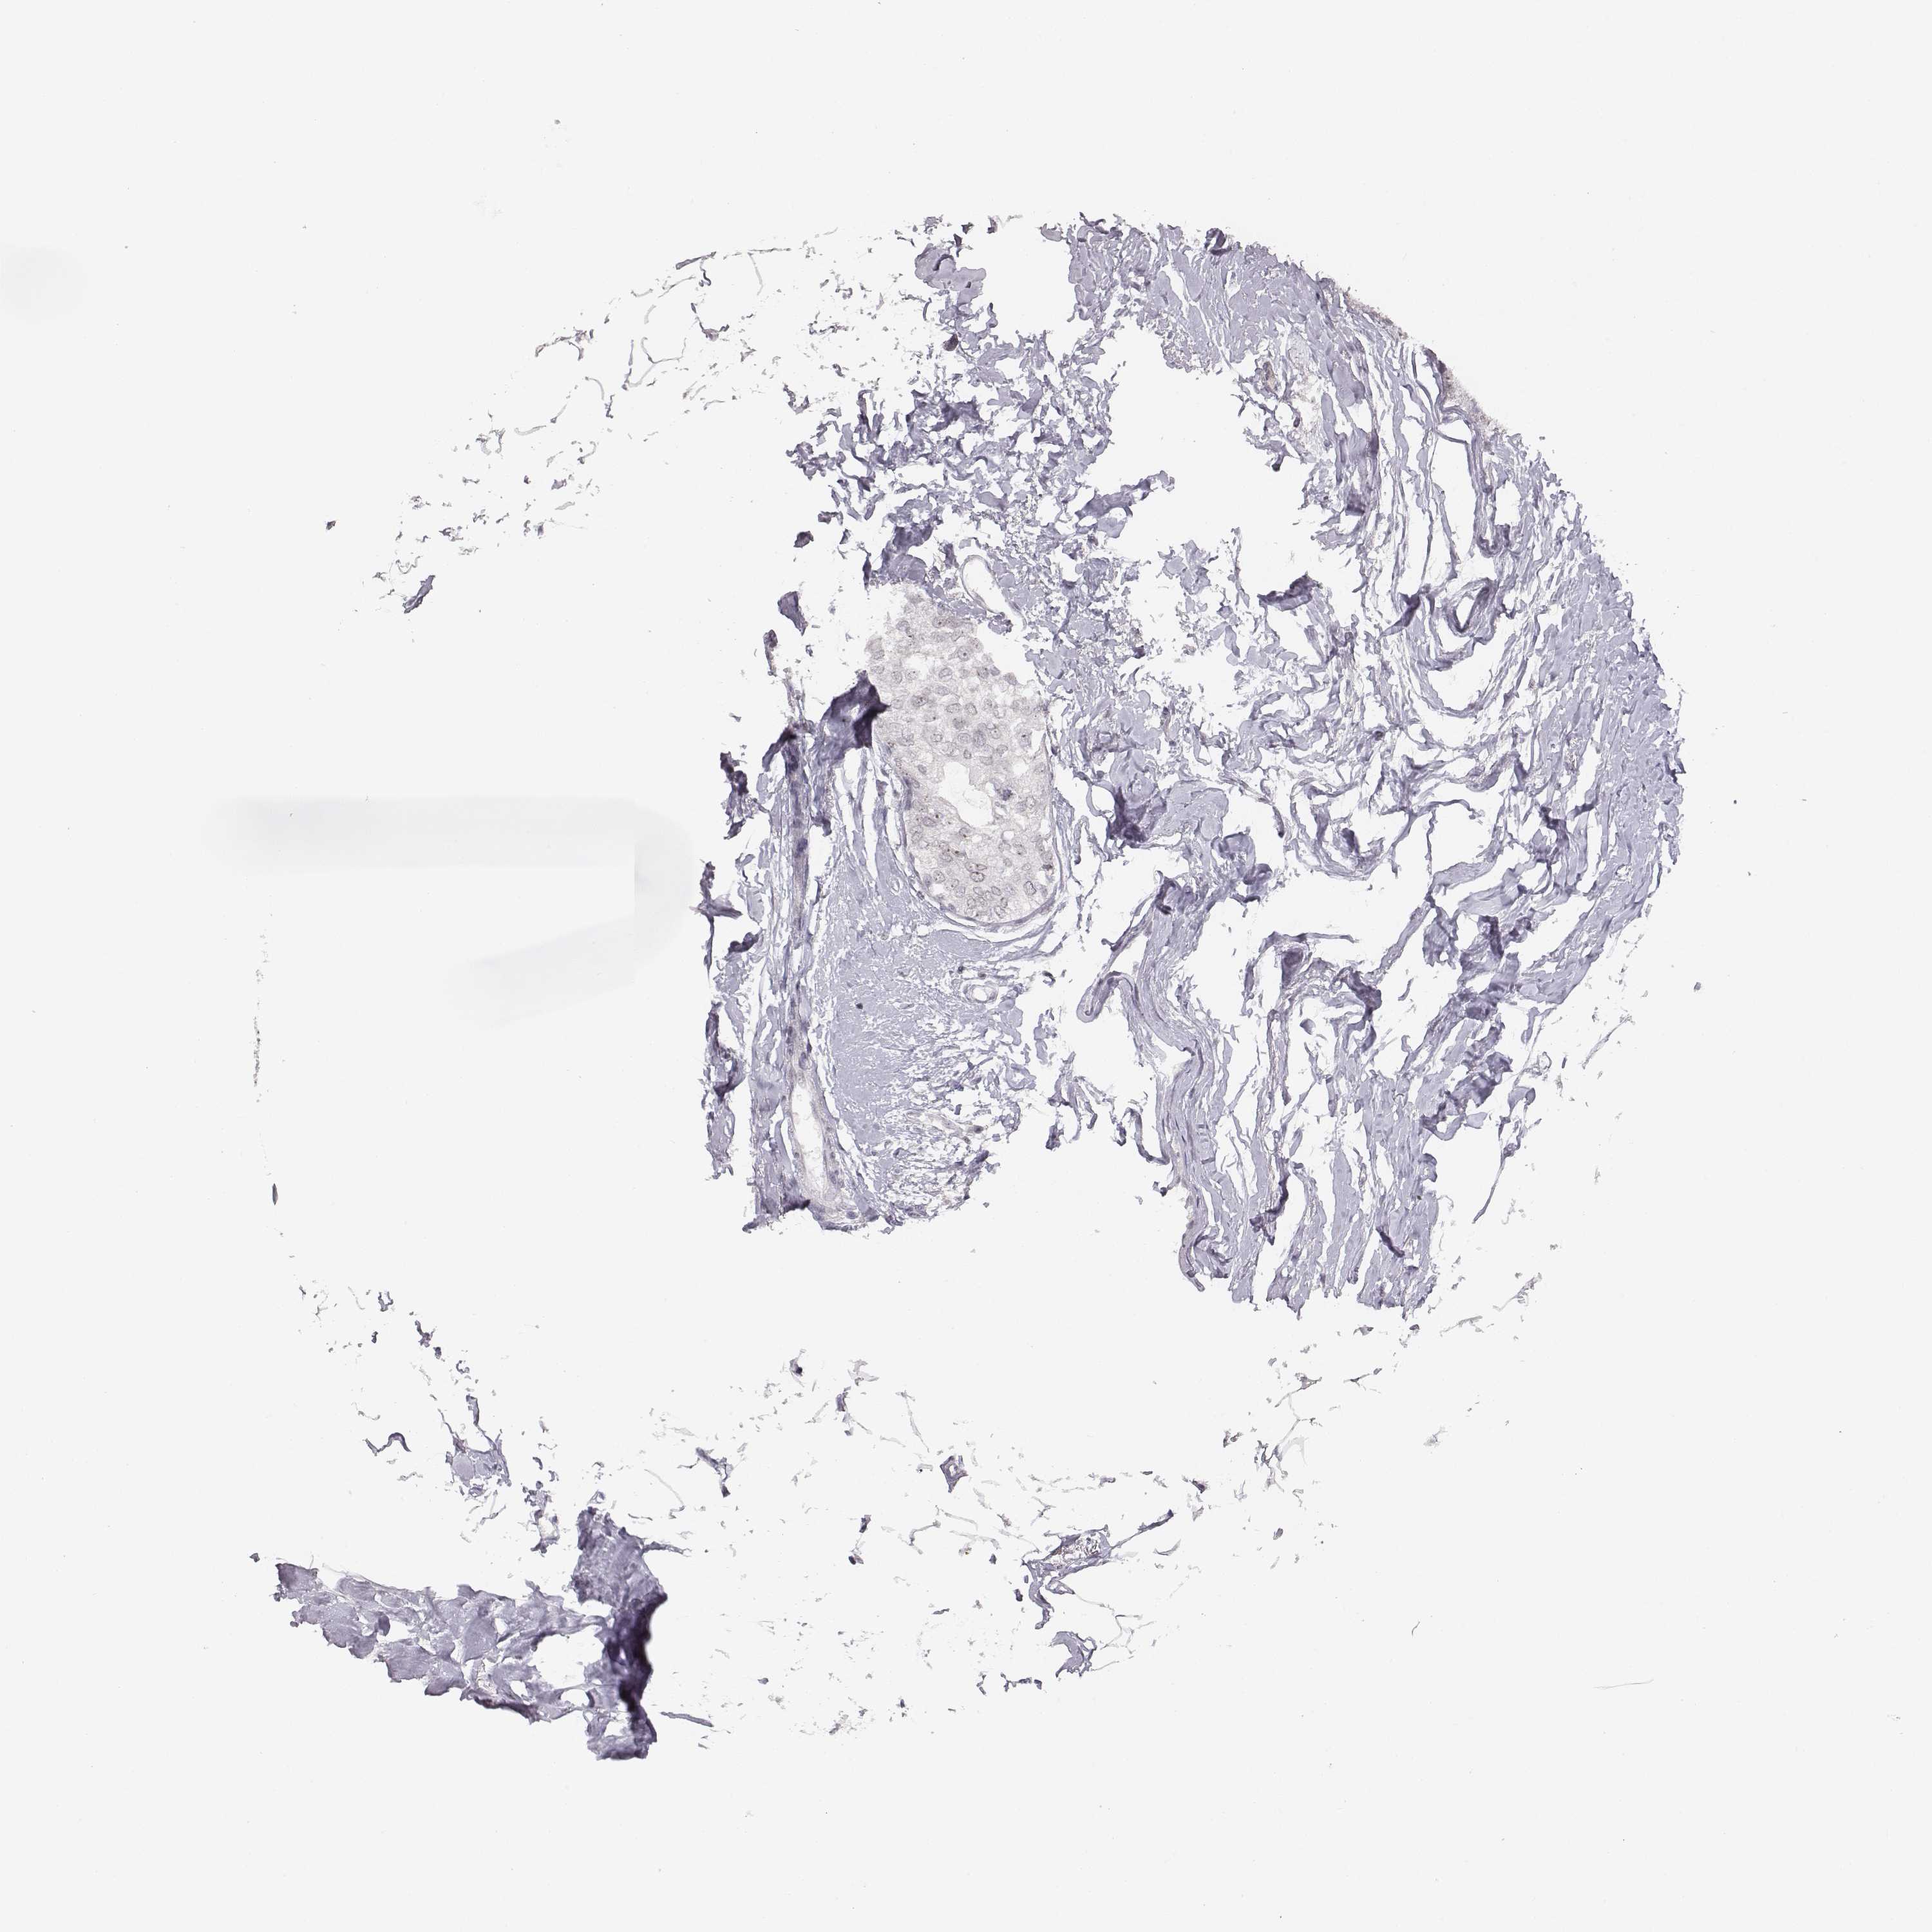

CANCER BREAST CANCER Show tissue menu

BRCA TCGA BRCA VALIDATION PROTEIN EXPRESSION

Breast cancer

Human cancer